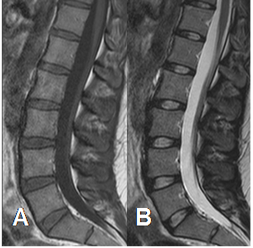

Fig 7. Señal anormal en STIR.

A: RM sagital en T1. Lesiones hipointensas en vértebras dorsales.

B: RM sagital en STIR. Aumento en la SI de las vértebras, por enfermedad metastásica de pulmón.